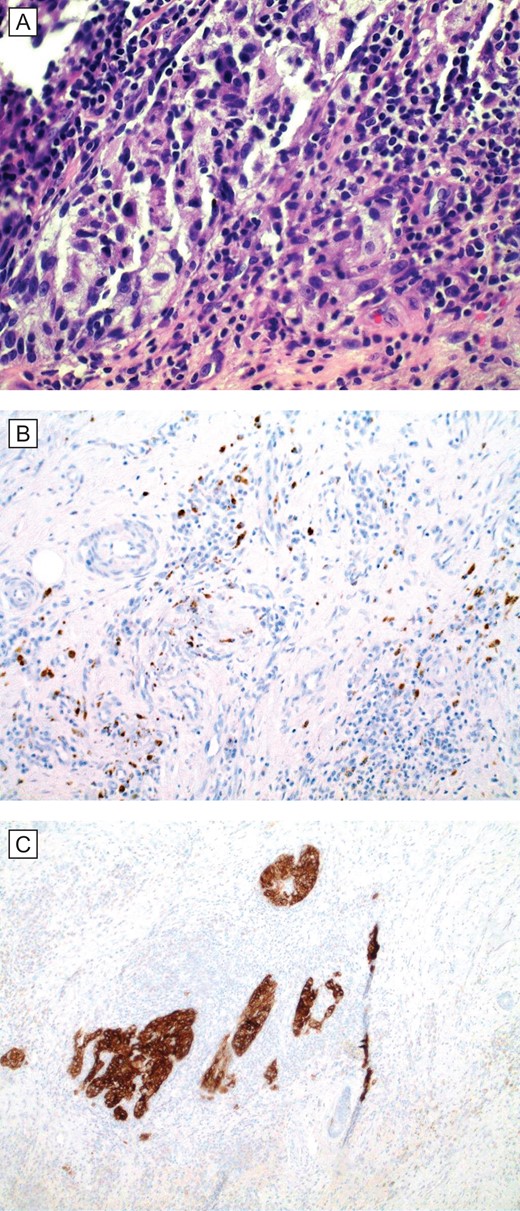

We report a 64-year-old white female with chronic right upper extremity lymphedema secondary to axillary lymphadenectomy after undergoing mastectomy for breast cancer who presents with two distinct skin lesions in the right arm and the forearm. Both of these skin lesions developed 4 year after surgery. Initially, punch biopsy was taken from one lesion, significant for nodular melanoma and the decision was made to excise both lesions. Right arm lymphoscintigraphy was performed using Technetium 99-labeled sulfur colloid with no obvious lymph node enlargement. Intraoperative gamma detection probe could not detect any lymph node activity in the right axilla. Both skin lesion removed during the same surgery with adequate safety margin. The final pathology was consistent with BCC with mixed nodular and superficial patterns in the right upper arm lesion and invasive melanoma with Breslow depth 1.1 mm and Clark level IV in the right forearm lesion. She had uneventful postoperative period and she was followed up clinically with no obvious recurrence (Figs 1 and 2).

(A) Histopathologic examination (H&E; original magnification: 400×) shows small foci of residual and scant melanoma cells. (B and C), special stains (IHC; original magnification: 400×) MART1/MelanA and HMB45, respectively, are cytoplasmic stains that highlight the presence of scattered melanoma cells in the dermis.